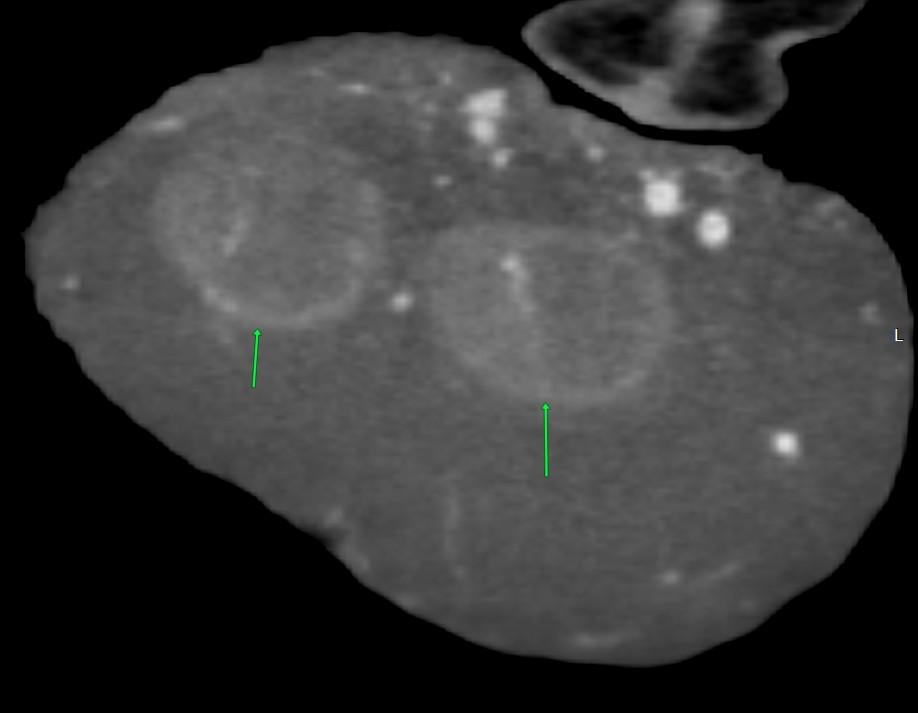

腫瘍内に2個、睾丸がありました

CT検査通り